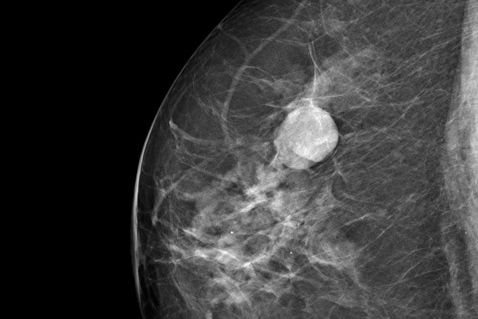

Spezielle Röntgenuntersuchung der weiblichen und männlichen Brust. Als Vorsorgeuntersuchung dient sie vor allem der Früherkennung von Brustkrebs, der häufigsten Krebserkrankung bei Frauen. Dank qualitativ stark verbesserter Technologie (Digitale Vollfeldmammographie) wurde die Strahlenbelastung während der letzten zehn Jahre erheblich reduziert und ermöglicht eine Nachverarbeitung der Röntgenaufnahmen mit verbesserter Detailauflösung. Tumorerkrankungen lassen sich dadurch heute schon in einem sehr frühen Stadium diagnostizieren und immer häufiger erfolgreich behandeln.

Von jeder Brust werden jeweils Bilder in zwei verschiedenen Projektionsebenen angefertigt. Dazu muss die Brust kurzfristig komprimiert werden. Unser Mammographiegerät verfügt über eine Vorrichtung, mit welcher die individuell benötigte Strahlendosis exakt bestimmt wird. Das Gerät wird täglichen Konstanzprüfungen unterzogen. Jährlich erfolgt eine Abnahme durch eine zertifizierte Prüfstelle. Nach Anfertigung der Bilder untersucht sie einer unserer Ärzte und bespricht den Befund anschließend mit Ihnen.

Bei dichtem Drüsengewebe oder unklarem Mammographiebefund sollte eine zusätzliche Abklärung mittels Sonographie (Ultraschall) erfolgen. In seltenen Fällen wird zusätzlich die Kernspintomographie (MR-Mammographie) eingesetzt.